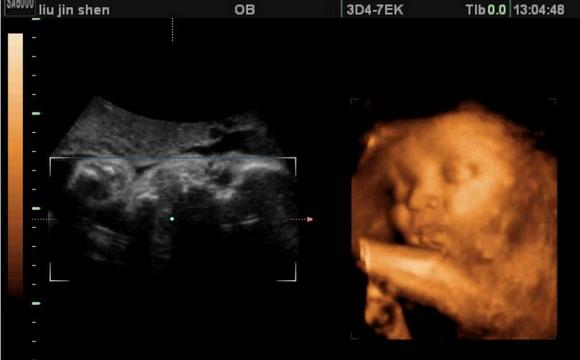

胎儿在孕晚期最突出的变化,可能就是体重的增加了。在前28周里,胎儿的体重可能还不到1千克,但从现在到出生,他的体重会增加2倍以上。

宝宝在这一周最大的变化是他可以睁开双眼了。宝宝的睫毛已经完全长出来了,如果子宫外有长时间的亮光,他会把头转向光束。宝宝的脂肪层在继续积累,为出生后在妈妈子宫外的生活做准备。不过,新生儿大部分时间都会闭着眼睛,睁开眼也只能看见脸前15~30厘米以内的东西。

宝宝的手指甲和脚趾甲已经完全长出来了。有些胎儿已经长了满头的头发,但有些只长出了淡淡的绒毛,这些都很正常。虽然宝宝现在占据了子宫里很大的地方,但他的胎动规律不应该有太大变化。如果你最近有初乳或前乳溢出,别忘了在胸罩里戴上哺乳垫。

宝宝的器官已经完全发育,并各就其位了。宝宝现在可能重2.7~3.4千克,长48.3~50.8厘米,像一个西瓜那么大了。他的抓握已经很有力了,很快你就会在他的小手抓住你的手指时注意到这一点!